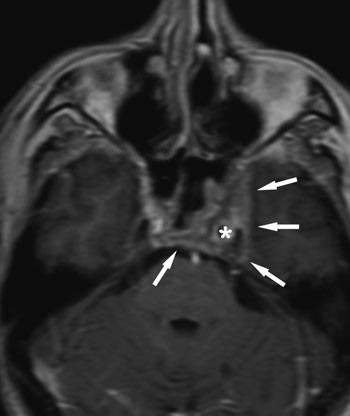

En 69 år gammel mann fikk plutselig dobbeltsyn. Ved nevrologisk undersøkelse ble det funnet venstresidig abducensparese og nedsatt sensibilitet tilsvarende venstre n. maxillaris og mandibularis. Magnettomografi viste en sparsomt kontrastoppladende tumor i venstre sinus cavernosus (fig 2). Svulsten lå rundt a. carotis interna og inn mot clivus. Endoskopisk, transsfenoidal biopsi viste atypiske celler som var positive for prostataspesifikt antigen. Videre utredning bekreftet diagnosen prostatakarsinom med solitær fjernmetastase til sinus cavernosus.